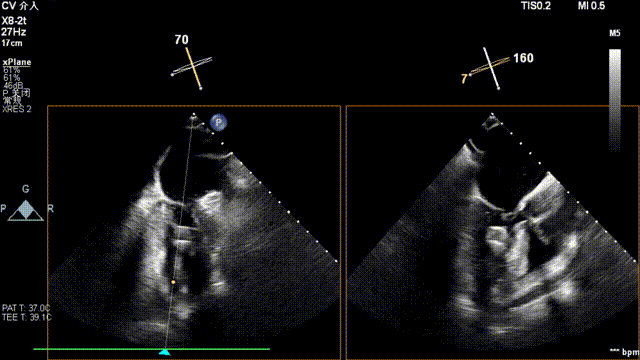

全麻后,二尖瓣夹合器系统在心前区的肋间切开3-4CM小切口,暴露心脏的心尖位置,送系统送入左心房,顺利到达病变二尖瓣区域。在经食道超声辅助下,术者通过反复评估二尖瓣反流位置、抓捕位置、反流程度,首先在2偏3区位置处于二尖瓣闭合线垂直进行巧妙夹合。在2区靠近3区位置处植入了1枚ValveClamp®MVC-IIf夹,最终评估评估反流降至轻度,平均跨瓣压差降至2mmHg,手术取得圆满成功。

术中超声(关键步骤)